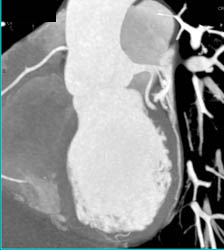

Patent Venous Bypass Graft